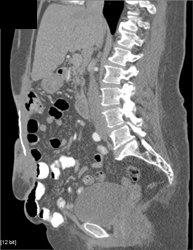

Drain Into Abscess Through Muscle